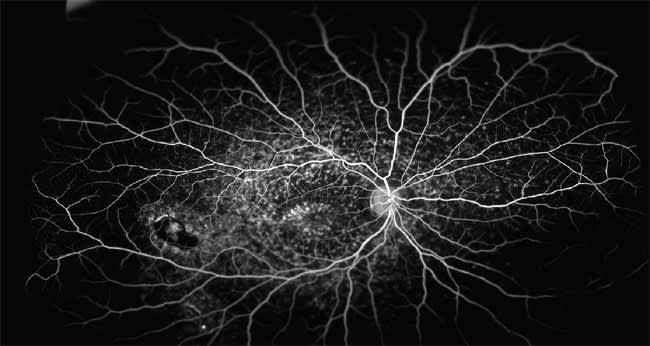

Figure 2. Superotemporal BRVO with secondary macular and peripheral ischemia. Note compensatory collateral formation.

Among patients with branch retinal and hemiretinal vein occlusions (BRVO, HRVO) who develop macular edema, a subset respond transiently to anti-VEGF or steroid therapy and develop recalcitrant macular edema. The answer to this problem may lie in the periphery, one study found.5 Untreated nonperfusion anterior to the globe equator was significantly associated with macular edema in patients with BRVO and HRVO. The study concluded that untreated areas of nonperfusion, many of them found in the periphery, may be the source of biochemical mediators that promote neovascularization and macular edema.